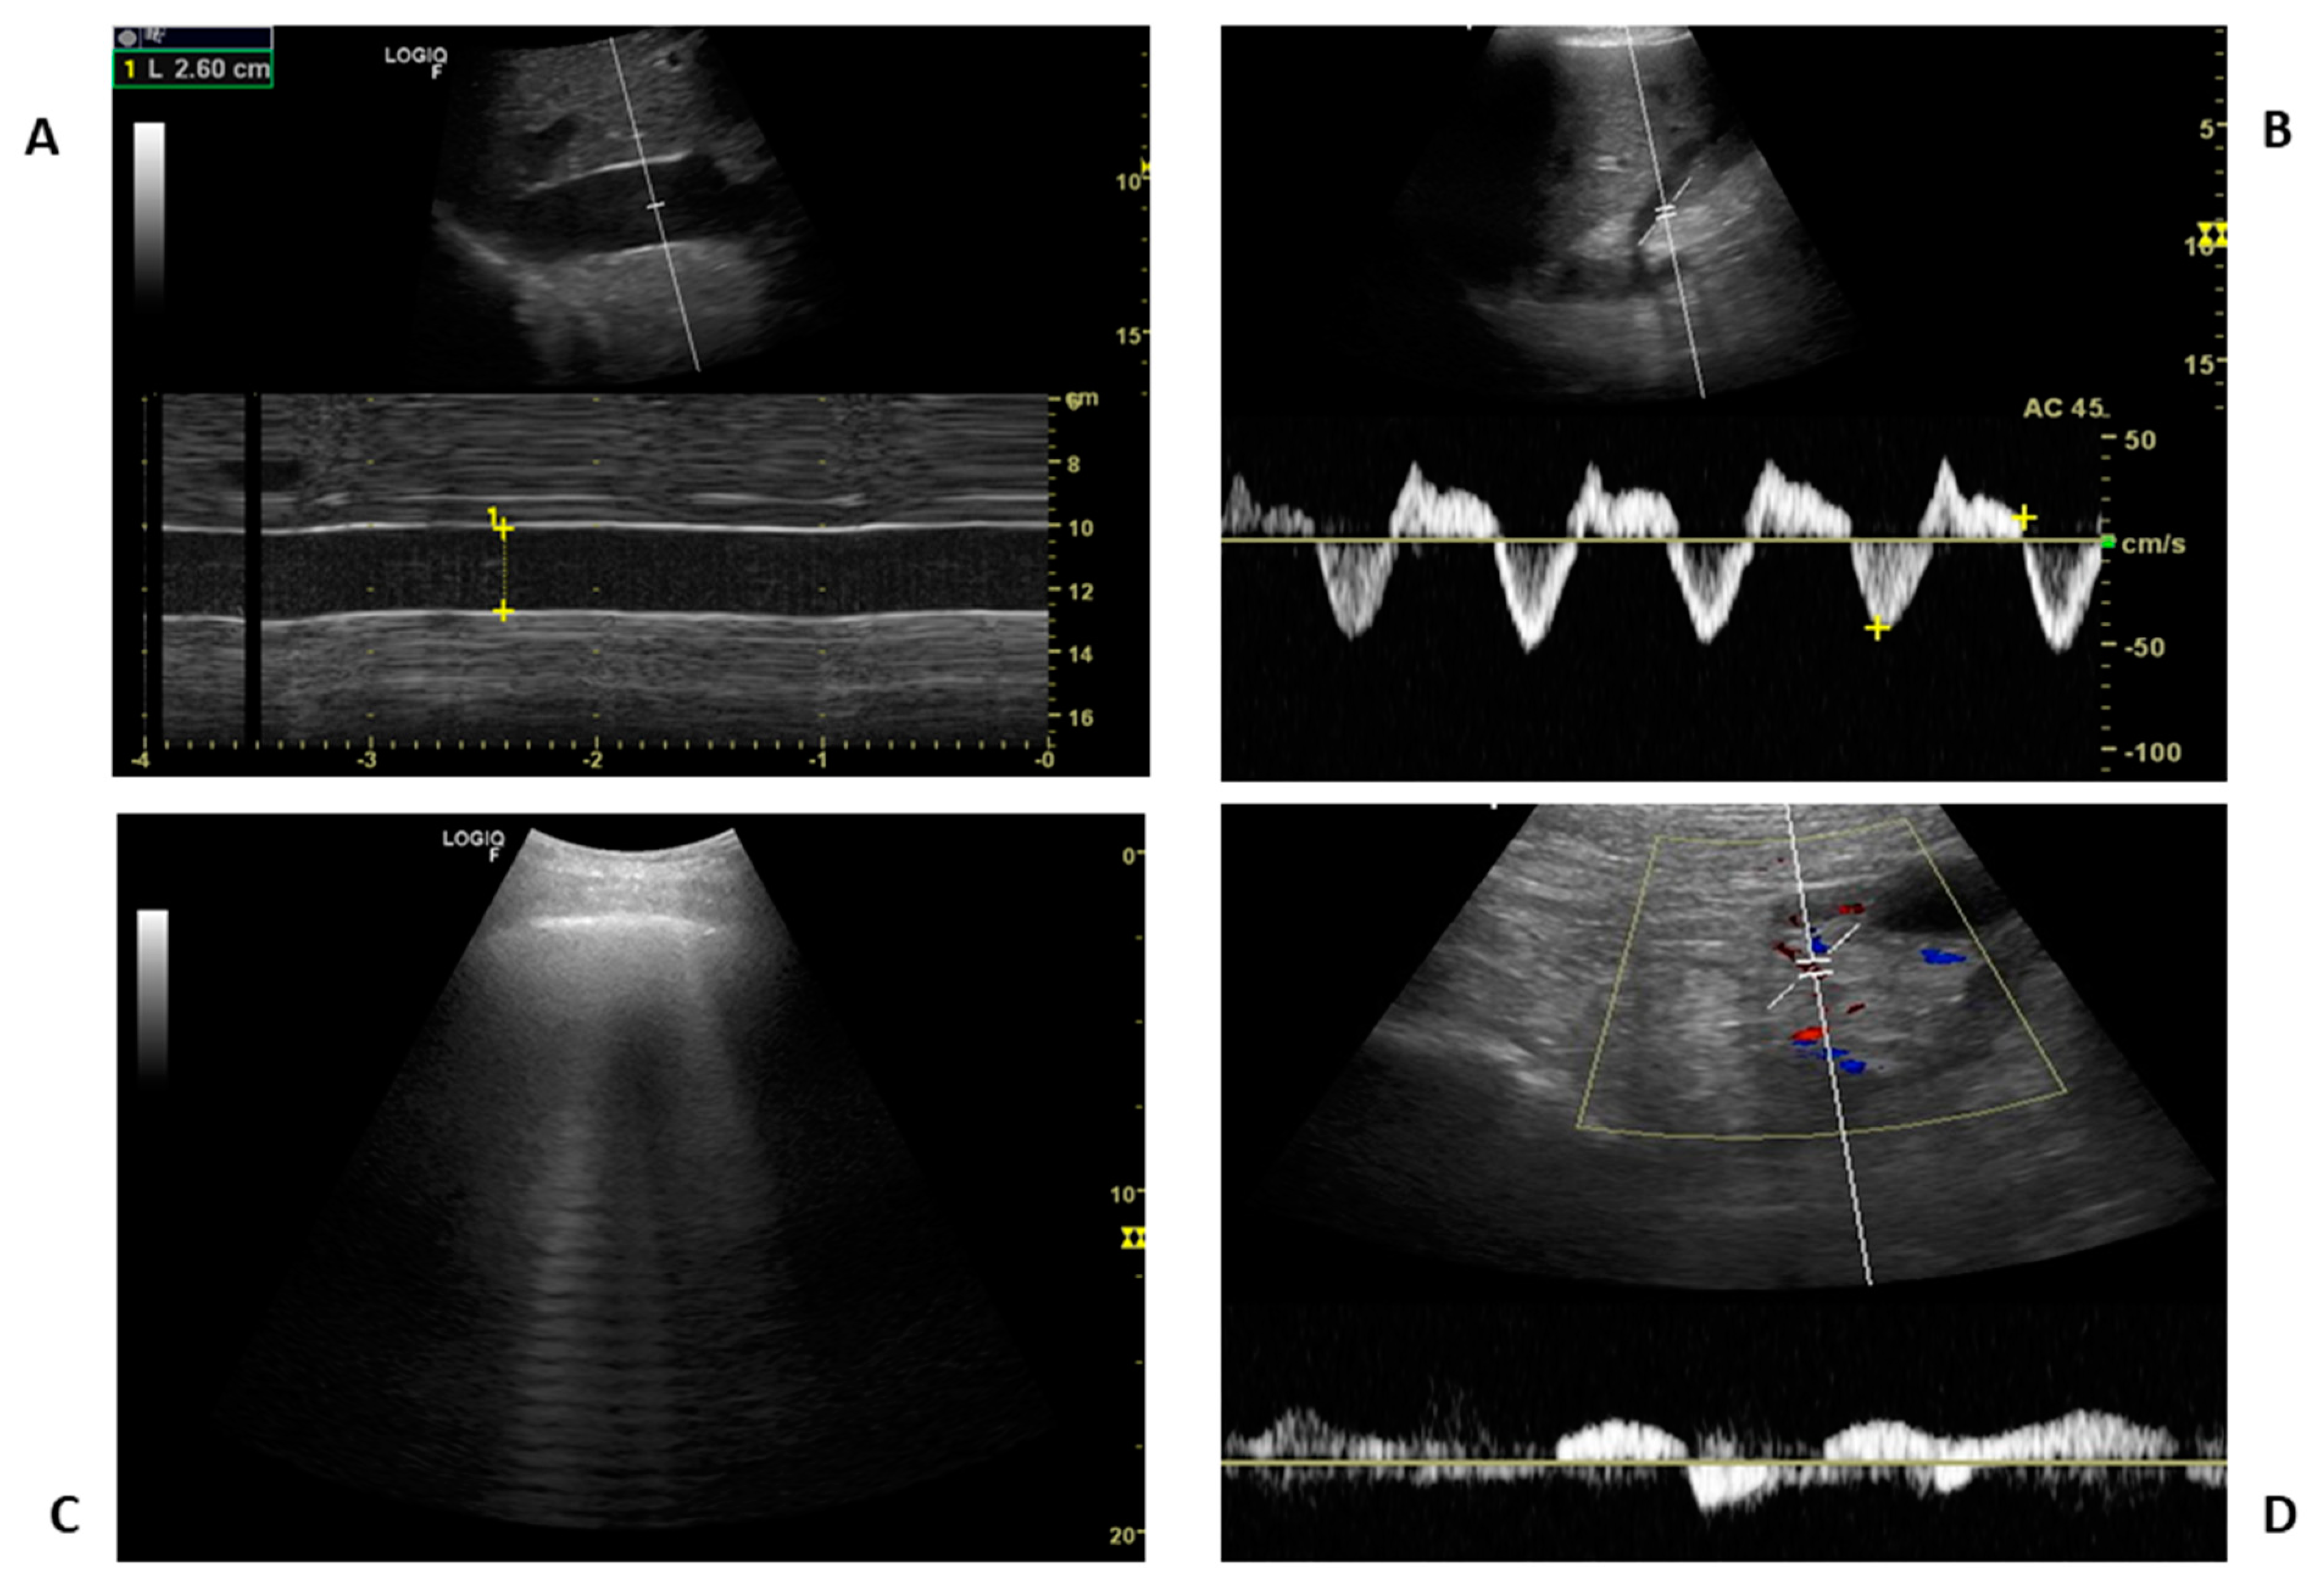

4. Ultrasound Technique, Static and Dynamic IVC Indexes